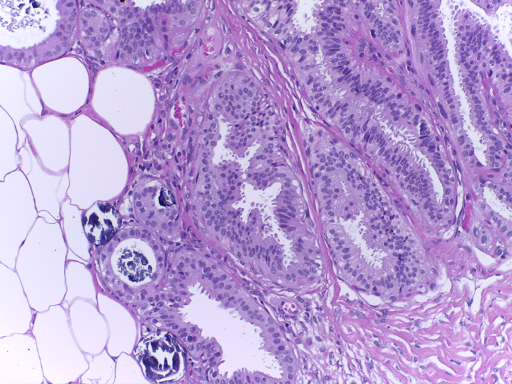

The microscopy dataset is composed of 400 training and 100 test images, with the four classes equally represented (see Fig. 2). All images were acquired in 2014, 2015 and 2017 using a Leica DM 2000 LED microscope and a Leica ICC50 HD camera and all patients are from the Porto and Castelo Branco regions (Portugal). Cases are from Ipatimup Diagnostics and come from three different hospitals (Hospital CUF Porto, Centro Hospitalar do Tâmega e Sousa and Centro Hospitalar Cova da Beira). The annotation was performed by two medical experts. Images where there was disagreement between the Normal and Benign classes were discarded. The remaining doubtful cases were confirmed via imunohistochemical analysis. The provided images are on RGB .tiff format and have a size of 2048×1536204815362048\times 1536 pixels and a pixel scale of 0.42 μ𝜇\mum ×\times 0.42 μ𝜇\mum. The labels of the images were provided in .csv format. Participants were provided with a partial patient-wise distribution of the images of the training set. The test data was collected from a completely different set of patients, ensuring a fairer evaluation of the methods. Note that the training set is an extension of the one used for developing the approach in [3].

Refer to caption

(a) Normal

(b) Benign

(c) In situ

(d) Invasive

Fig. 2: Examples of microscopy images from the BACH dataset.